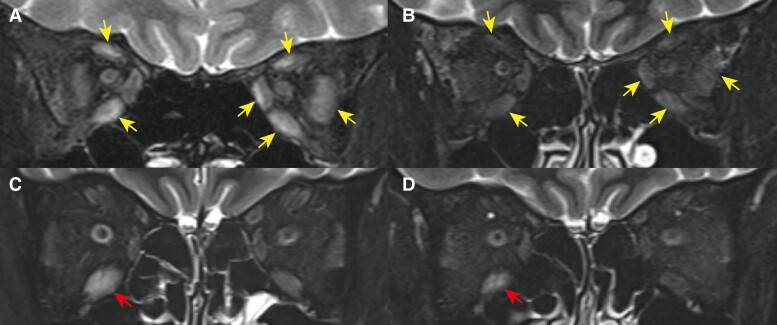

SARS-CoV-2感染可能引发自身免疫性疾病。我们报告一例SARS-CoV-2感染后Graves眼病(GO)和重症肌无力(MG)的合并加重。43岁女性,复视、眼球突出、眼睑肿胀。血液检查显示甲状腺毒症和促甲状腺激素受体抗体阳性,眼眶磁共振(MRI)显示眼外肌肿大。因此,她被诊断为GO转介到我们医院。甲泼尼龙脉冲治疗(MPT)联合眼眶放射治疗3周,眼部症状得到改善。41周时,患者感染了SARS-CoV-2,并感到复视和上睑下垂突然恶化。MRI显示右下直肌肿大。疑似GO再次行MPT和眼眶放疗3周,但上睑下垂改善不足。血清抗乙酰胆碱受体和抗肌肉特异性酪氨酸激酶抗体均为阴性,但通过反复神经刺激试验和冰袋试验进一步评估患者,诊断为双血清阴性MG。吡哆斯的明治疗可显著改善上睑下垂。SARS-CoV-2感染可加重MG和GO。SARS-CoV-2感染后的眼部症状需要仔细诊断,特别是双血清MG阴性时。

SARS-CoV-2 infection could trigger autoimmune disease. We report a case of concomitant exacerbation of Graves orbitopathy (GO) and myasthenia gravis (MG) after SARS-CoV-2 infection. A 43-year-old woman had diplopia, proptosis, and swollen eyelids. Blood tests showed thyrotoxicosis and positive thyroid-stimulating hormone receptor antibodies, and orbital magnetic resonance imaging (MRI) showed enlarged extraocular muscles. She was therefore referred to our hospital with diagnosis of GO. Methylprednisolone pulse therapy (MPT) in combination with orbital radiotherapy were performed for 3 weeks, and ocular symptoms improved. At 41 weeks, the patient was infected with SARS-CoV-2 and felt sudden worsening of diplopia and ptosis. MRI showed an enlarged right inferior rectus muscle. MPT and orbital radiotherapy were performed again for 3 weeks for the suspected GO, but there was insufficient improvement of the ptosis. Serum antiacetylcholine receptor and anti-muscle-specific tyrosine kinase antibodies were negative, but the patient was further evaluated with repetitive nerve stimulation test and ice pack test, and diagnosis was double-seronegative MG. Pyridostigmine treatment led to dramatic improvement of the ptosis. SARS-CoV-2 infection could exacerbate MG as well as GO. Careful diagnosis is required for ocular symptoms after SARS-CoV-2 infection, especially when there is double-seronegative MG.